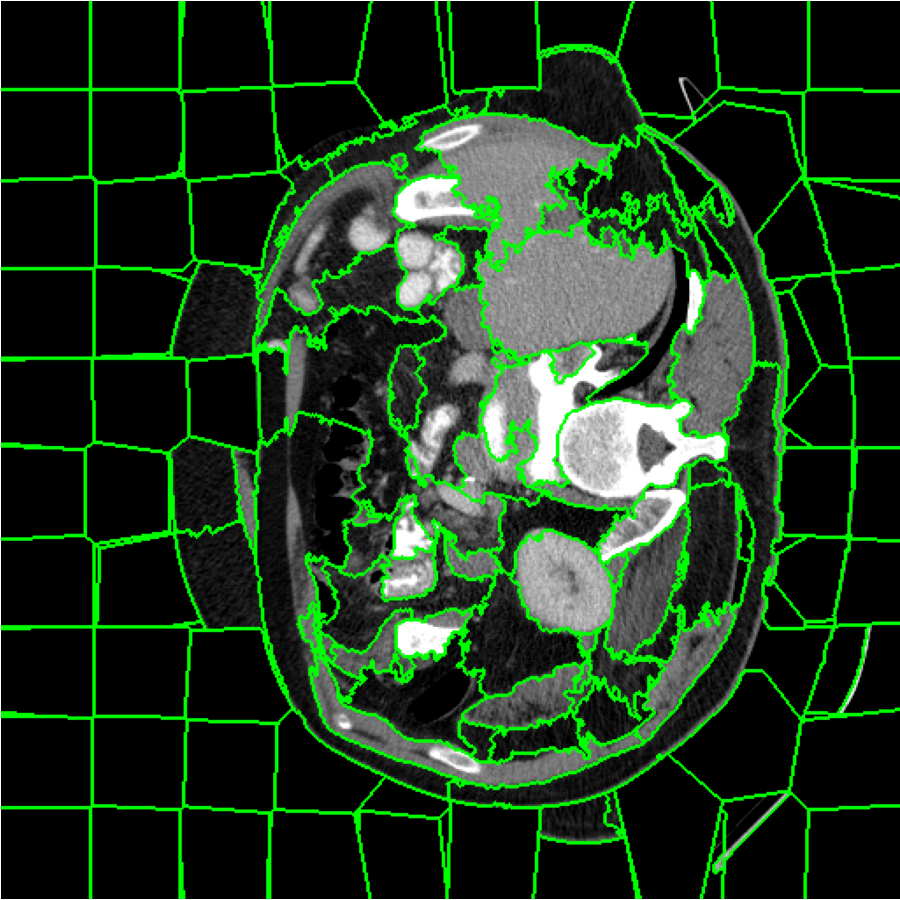

Figure 4: (a)(b)(f)(g) Training images; (c)(d)(e)(h)(i)(j) Generated augmented images with outlined superpixel grids in green color. The numbers of superpixels, l1l_{1} and l2l_{2} corresponding to either training image, are fixed here for visualization.

In general, increasing the number of superpixel, ll, leads to a finer granularity that provides less semantic information but more contour information. Conversely, decreasing in the superpixel number results in a coarser granularity that provides less contour information but more semantic information. As can be seen in Figure 4, the superpixels in Figure 4(c) and Figure 4(h) have a higher level of semantic information but lower capacity of contour information when the superpixel number, denoted by ll, is relatively small. In Figures 4(e) and 4(j), the number of superpixels, ll, is relatively large. Consequently, although the synthetic superpixel maps have detailed boundaries, they lack semantics. For images with a large amount of fine-grained content or granularity, it is recommended to use a relatively large number of superpixels, where each superpixel is relatively small. Conversely, a small number of superpixels can also be used, with each superpixel being relatively large. In our method, the number of superpixels ll for each image is randomly determined according to a uniform distribution lU(lmin,lmax)l\sim U(l_{min},l_{max}) instead of setting it as constant. This is easier to tune and can increase the diversity of the augmentation space. It can also improve the robustness of our method. The quantitative analysis is shown in Table 8.